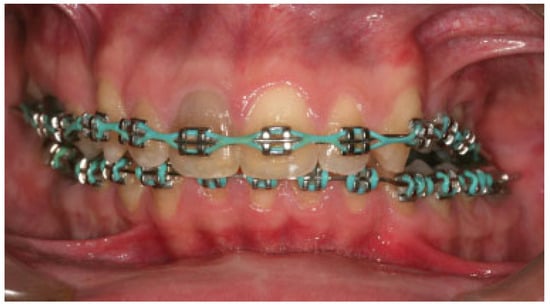

:Case Report